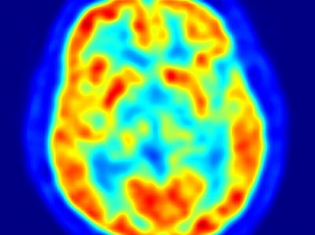

(RxWiki News) Researchers at UCLA have discovered a brain-scan technique that could help detect dementia in adults with Down syndrome. The researchers created a chemical marker, known as FDDNP.

This marker binds to plaques and fibrous tangles in the brain, which are hallmarks of Alzheimer’s disease and other forms of dementia. They then were able to see the tangles and plaque through positron emission tomography (PET)—which all adds up to a new way of diagnosing dementia's early signs.

In the study, researchers administered the chemical marker intravenously and performed PET brain scans on 19 adults with Down syndrome without dementia, 10 healthy control subjects and 10 patients with Alzheimer’s disease. The investigators found more brain tangles and deposits in the adults with Down syndrome when compared with healthy control subjects, and more tangles and deposits in the areas of the brain controlling memory, behavior and reasoning in Down syndrome adults compared with Alzheimer’s patients.